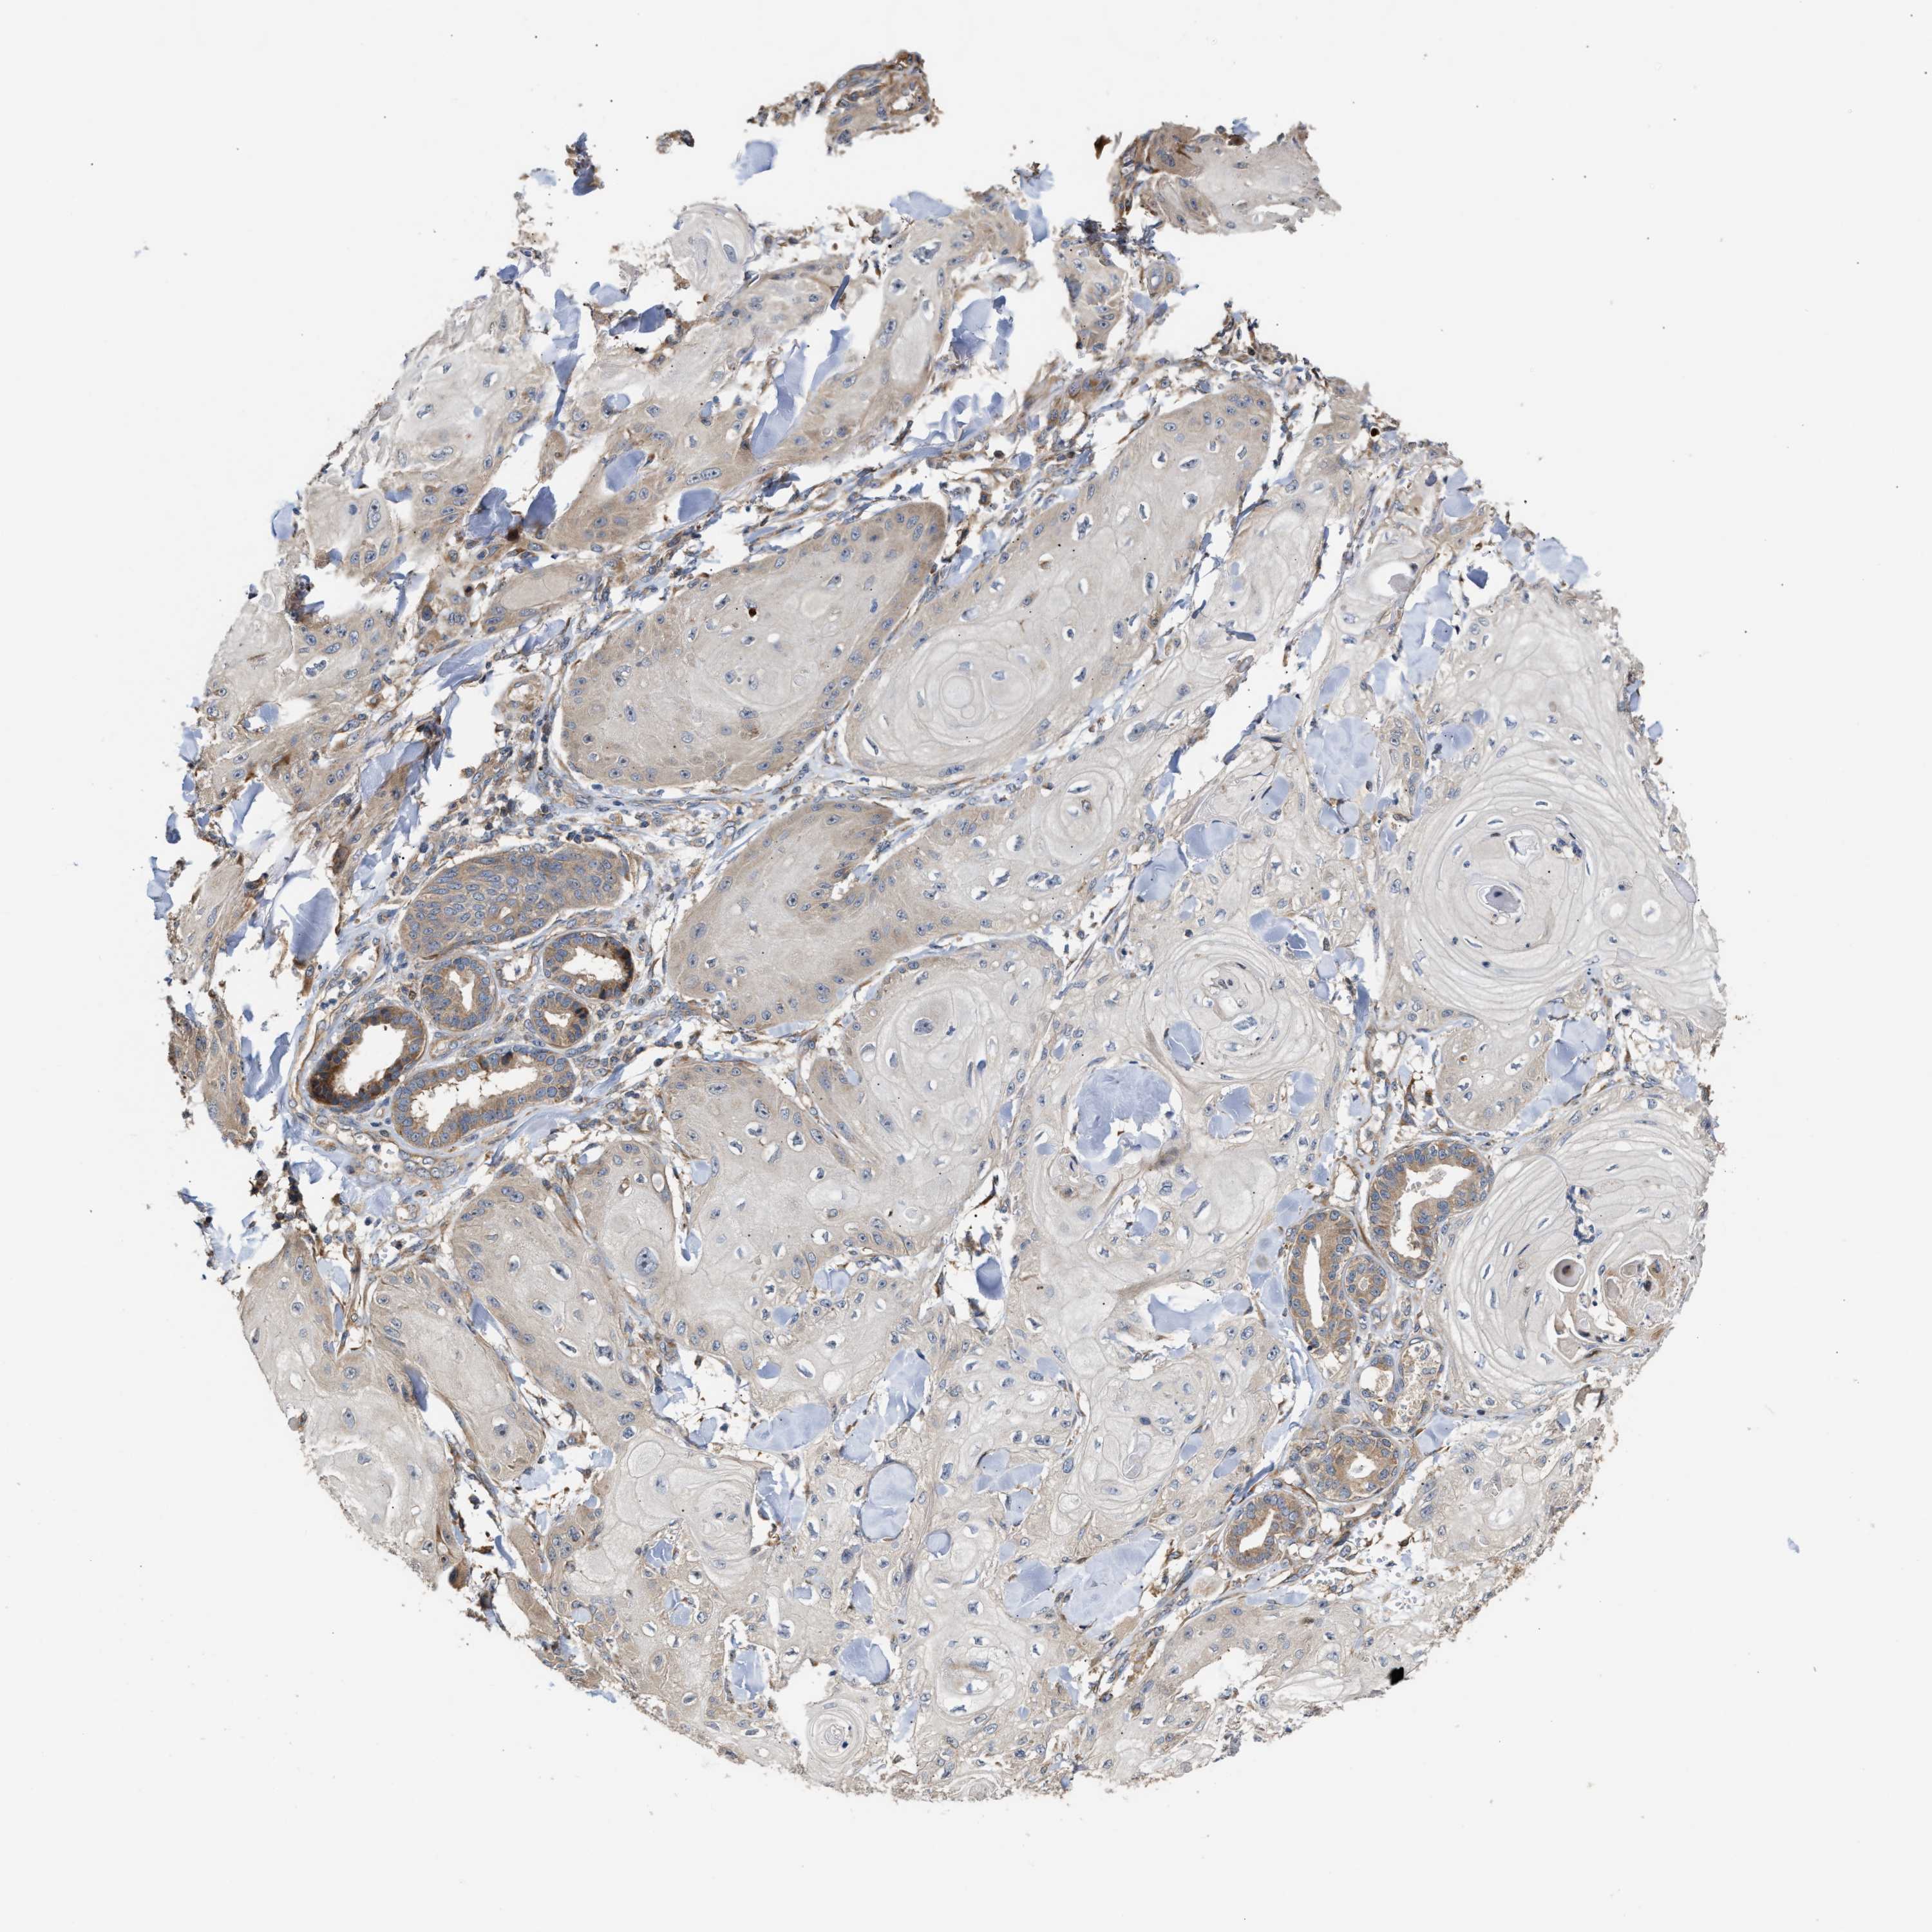

SKIN CANCER - Protein expressioni

A mouse-over function shows sample information and annotation data. Click on an image to view it in a full screen mode. Samples can be filtered based on level of antibody staining by selecting one or several of the following categories: high, medium, low and not detected. The assay and annotation is described here.

Antibody stainingi

Antibody staining in the annotated cell types in the current human tissue is reported as not detected, low, medium, or high, based on conventional immunohistochemistry profiling in selected tissues. This score is based on the combination of the staining intensity and fraction of stained cells.

Each image is clickable and will lead to virtual microscopy that enables deeper exploration of all samples and also displays staining intensity scores, fraction scores and subcellular localization as well as patient and tissue information for each sample.

Antibody HPA020430

Staining

High

Medium

Low

Not detected

Intensity

Strong

Moderate

Weak

Negative

Quantity

>75%

75%-25%

<25%

None

Location

Nuclear

Cytoplasmic/membranous

Cytoplasmic/membranous,nuclear

Squamous cell carcinoma in situ, NOS

Squamous cell carcinoma, NOS

Squamous cell carcinoma, metastatic, NOS

Basal cell carcinoma